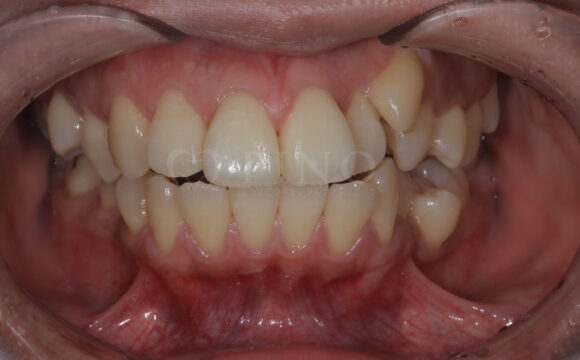

症例2:ワイヤー矯正後の後戻りが気になる(50代女性)

主訴 ワイヤー矯正後に後戻りが気になる 診断名 叢生 治療方法 マウスピース部分矯正 抜歯 なし オルソパルス なし 治療期間 10ヶ月 費用 436,000円+補綴費用360,000円 副作用・注意点 矯正後の後戻りを防ぐためリテーナーの使用が必要となる 備考 1年4ヶ月で補綴も完了した -